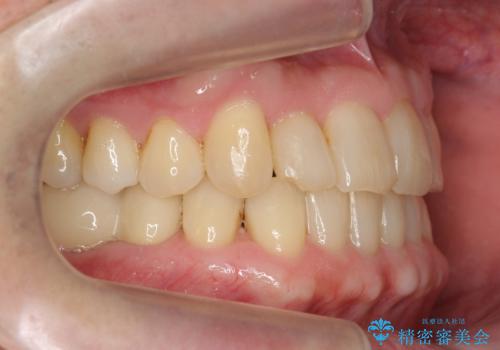

矯正治療後、右下のインレーブリッジおよび左下の銀歯のやりかえを行なっています。

右上の八重歯は、右上の奥歯を矯正用ミニスクリューを用いて遠心移動を行い解消しました。

下の前歯はIPR(エナメル質を薄く削り歯を小さくする処置)を行なっています。